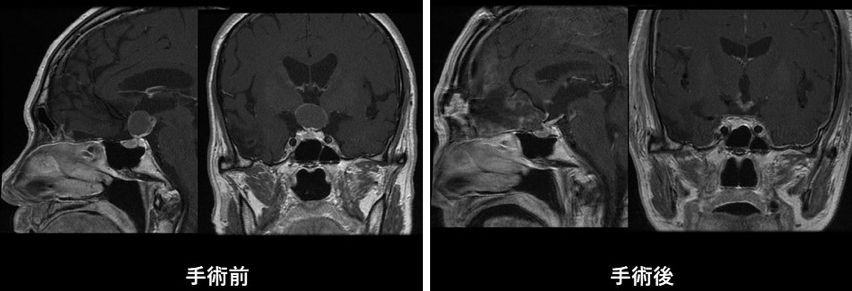

プロラクチン産生腺腫(プロラクチノーマ)を除く下垂体腺腫に対しては、基本的に内視鏡下経鼻的下垂体腫瘍摘出術を行います。当施設では、最新の内視鏡手術装置および手術用ナビゲーションを常備しており、狭い術野でも安全かつ確実に手術を行うことが可能です。最近では高齢の患者さんも増えており、手術前には内科や麻酔科とも十分相談し耐術能についてもきちんと評価した上で手術を受けていただきます。この手術では、鼻孔から内視鏡を挿入し、蝶形骨洞(副鼻腔の一部)を経由してトルコ鞍という腫瘍が収まっている頭蓋骨のくぼみに到達します。この骨に1.0〜1.5cm程度の小さな穴を開け、正常下垂体や周囲の重要な血管(海綿静脈洞や内頚動脈など)を傷つけないようにしながら腫瘍を最大限に摘出します。摘出後の空洞には、通常右下腹部から採取した脂肪片を埋めた後、手術用の接着剤(フィブリン糊)でしっかりと固定します。最後に鼻腔内をタンポンガーゼでパッキングします。この方法は、脳を直接触らないため比較的安全な手術と考えますが、髄液漏、尿崩症や鼻出血などの合併症があります。

手術によって全摘出できれば治癒が可能ですが、手術の難易度はかなり高いです。手術は開頭手術を行うことが多いですが、小さい腫瘍の場合には内視鏡を用いて鼻から手術を行うこともあります。腫瘍が残存したり再発した場合には放射線治療を行います。手術後にホルモン分泌障害がおこった場合には、ホルモンの補充が必要になります。